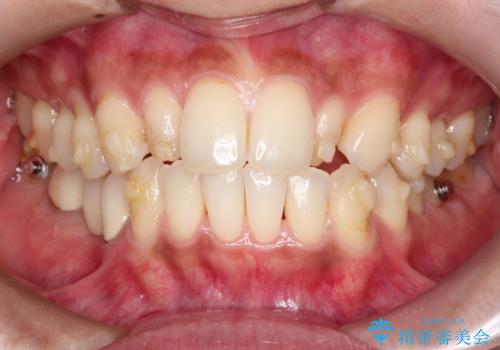

【インビザライン】矮小歯を有する方の矯正治療

- 前歯の凸凹を主訴に来院されました。

元々、歯が小さかったため矯正終了後にセラミックにて修復治療を行う治療計画をたてインビザラインにて治療を行いました。

今回はスペースを作るために歯列の拡大をメインでおこなっています。